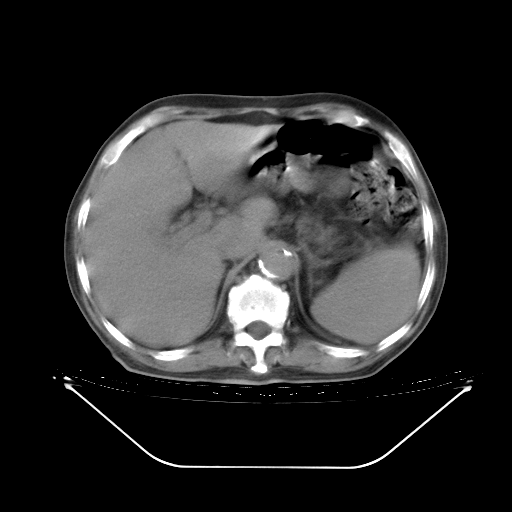

今天复查肺部CT,发现双肺广泛磨玻璃样改变。所以我把3月19日和5月9日相隔50天的肺部CT上传。请大家会诊。

5月9日肺部CT(在4月27日齐鲁医院肺部CT描述部分肺组织磨玻璃样改变,12天后肺组织广泛磨玻璃样改变)